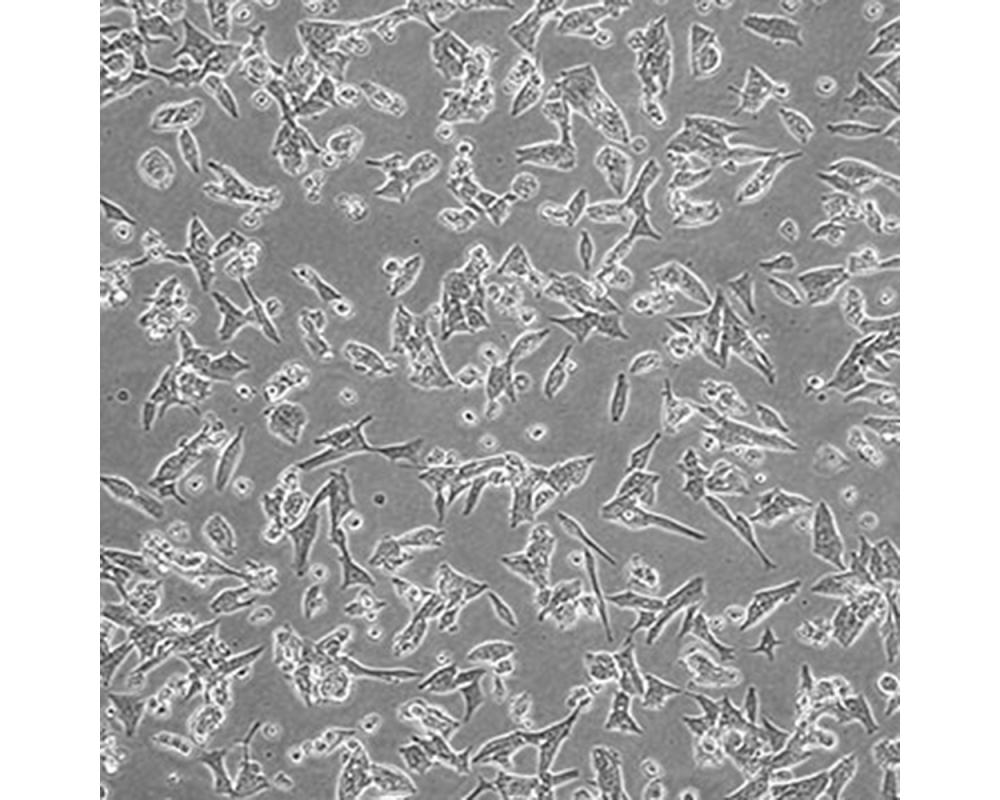

中文名稱 人前列腺癌細(xì)胞

組織來源 前列腺癌;男性

形態(tài)特征 上皮細(xì)胞

生長特性 貼壁生長

特征特性 1997從一位不受激素影響的前列腺癌患者脊椎轉(zhuǎn)移灶中建立了這株細(xì)胞。先在小鼠中進行異種移植傳代,隨后進行體外培養(yǎng)。體內(nèi)及體外都對雄性激素敏感。

培養(yǎng)條件 DMEM(高糖)+10%FBS,氣相:空氣,95%;二氧化碳,5%。溫度:37攝氏度。

傳代方法 消化3-5分鐘。1:2。3天內(nèi)可長滿。